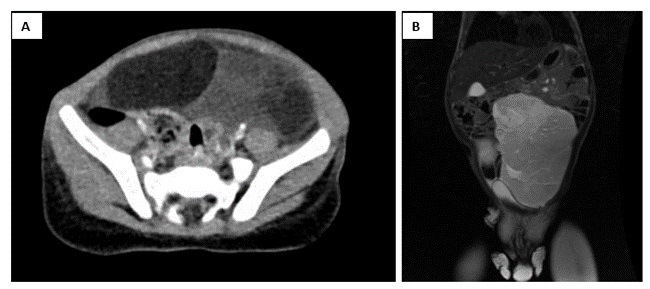

Dada la persistencia de los hallazgos clínicos se amplía el estudio solicitando ecografía abdominal e interconsulta a Gastroenterología infantil, desde donde se programa estudio genético de enfermedad celiaca y endoscopia digestiva alta, que no llega a realizarse ante el resultado de la ecografía abdominal de lesión compatible con tumoración de gran tamaño. Se realiza estudio de extensión de la tumoración, mediante tomografía computerizada (TC) abdominal (Fig. 2A), donde se observa masa sólida desde región subhepática hasta hipogastrio, con apariencia de estirpe grasa, y resonancia magnética (RM) abdominal (Fig. 2B) en la que se objetiva una masa centroabdominal con efecto masa sobre asas intestinales y vejiga, sin infiltrar estructuras, con márgenes bien definidos y consistencia grasa, que sugiere lipoblastoma mesentérico.

| Figura 2. Lipoblastoma mesentérico. (A) Tomografía computarizada (TC) abdominal: tumoración de 12 x 5 x 12 cm que ocupa desde región subhepática hasta hipogastrio. (B) Resonancia magnética (RM) abdominal: masa centroabdominal de 14 x 15 x 6 cm con efecto masa sobre asas intestinales y vejiga, sin infiltrar estructuras |

|---|

![]() |